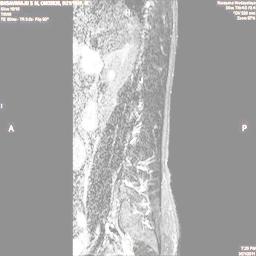

The proposed algorithm uses HSV color space to enhance spinal cord images since this color space offers many advantages such as color separation from intensity, reduced color distortion and efficient enhancement. The algorithm proposed takes advantage of this color space by performing enhancment operation on the intensity or value component and preserving the color information. The first column of Fig. 3 shows the original spinal cord test images followed by the extraction of value component presented in second column. Next, the third column of Fig. 3 shows the value component enhanced using the proposed multirate multiscale retinex algorithm. The modified version of the retinex algorithm presented here is capable of producing high quality reconstructed pictures, far better than the other researchers method.

The developed algorithm presented in the previous section was coded using Matlab Version 8.0. The experiment was conducted by considering poor quality spinal cord images of having various lesions. The first column of Fig. 4 shows the axial view of neck spinal cord images of size pixels, respectively. The second column of Fig. 4 presents the same images enhanced using histogram equalization. As is evident from the results presented, the histogram equalization method performs global image enhancement operation which improves the contrast of an image but at the cost loss in image details. The third column of Fig. 4 shows the MSR based spinal cord image enhancement. It can be seen that from the result presented, MSR scheme improves the details that are not clearly visible in histogram equalization technique. In general, image enhancement achieved by MSR method is better compared to histogram equalization. However, the MSR method voilates gray world assumption. Therefore, the image enhanced by this scheme appears to be grayish. Although, numerous work have been reported for solving the problem due to gray world voilation, no work seems to developed for complete elimination.

The fourth column of Fig. 4 shows the image enhanced using Chao et al. []. It can be seen from the results presented that the reconstructed images of Chao’s method have black spots. The appearance of these dark patches degrades the visual quality of the enhanced image. The image enhanced using proposed multirate multiscale retinex image enhancement method presented in the fifth column of Fig. 4, overcomes the drawback of the Chao’s method. As we can see from the simulation results, image enhancement achieved by the proposed method has improved details with significant contrast enhancement. The enhanced images from the proposed method provides information to physicians, radiologists and researchers for various types of pathology detection.